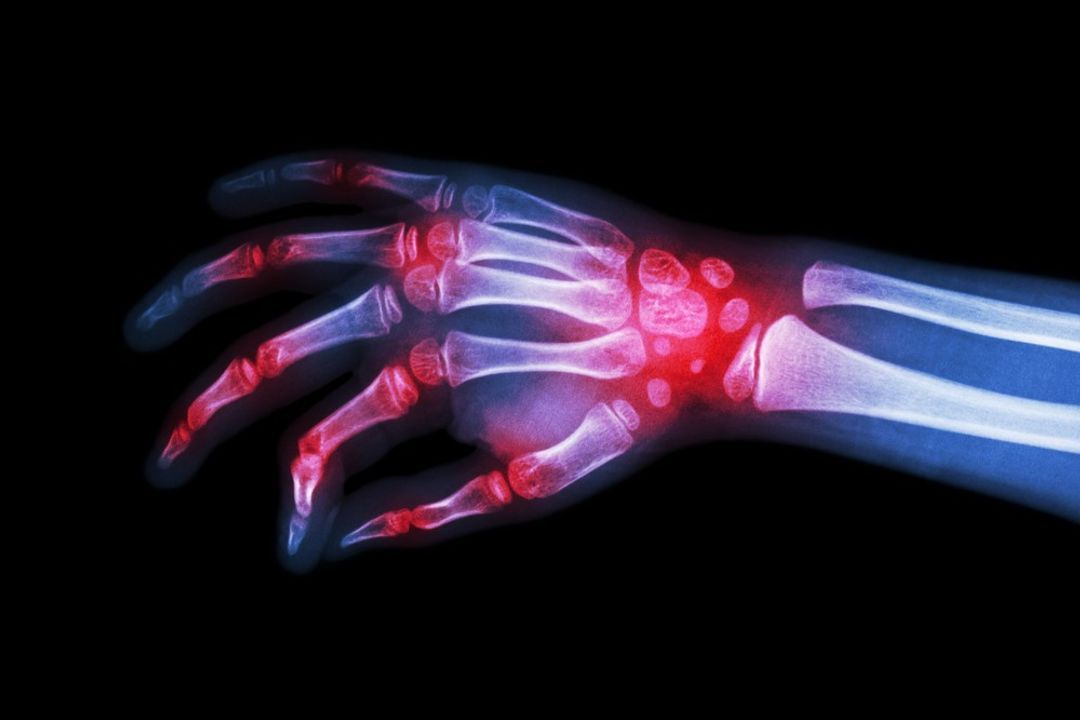

X-ray imaging can indirectly detect certain inflammatory conditions, particularly those affecting the joints and bones. While X-rays cannot directly visualise inflammation, they can reveal changes in the tissues and bones that suggest an ongoing inflammatory process.

Rheumatoid arthritis

X-rays can reveal signs of joint inflammation in rheumatoid arthritis, such as joint space narrowing, bone erosions and periarticular osteopenia (areas of low bone density around the joint).